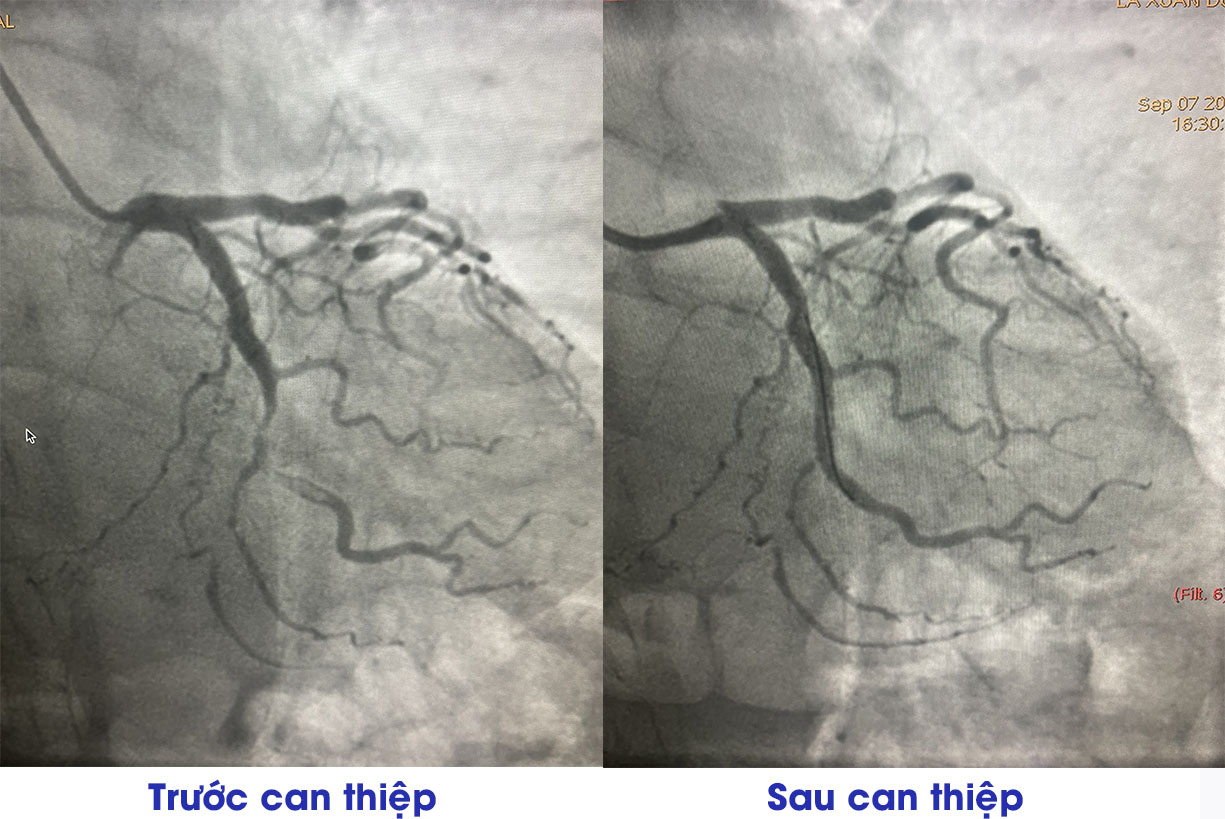

Trong quá trình theo dõi điều trị, bệnh nhân xuất hiện cơn đau ngực điển hình, các bác sĩ tiến hành cận lâm sàng phù hợp. Ông D. được chẩn đoán nhồi máu cơ tim, chỉ định chụp và can thiệp động mạch vành dưới DSA.

Hình ảnh chụp động mạch vành của người bệnh nhồi máu cơ tim trước và sau can thiệp (Ảnh: BV)

Hình ảnh chụp động mạch vành của người bệnh nhồi máu cơ tim trước và sau can thiệp (Ảnh: BV)Kết quả chụp động mạch vành cho thấy CTO LCX3, hẹp 90 – 99% LCX2- OM2, có huyết khối nhiều, hẹp 70% LAD2, hẹp 80% RCA2. Người bệnh đã được Ekip bác sĩ của Trung tâm Tim mạch – Bệnh viện Đa khoa tỉnh Phú Thọ tiến hành can thiệp hút huyết khối, nong, đặt stent động mạch vành.